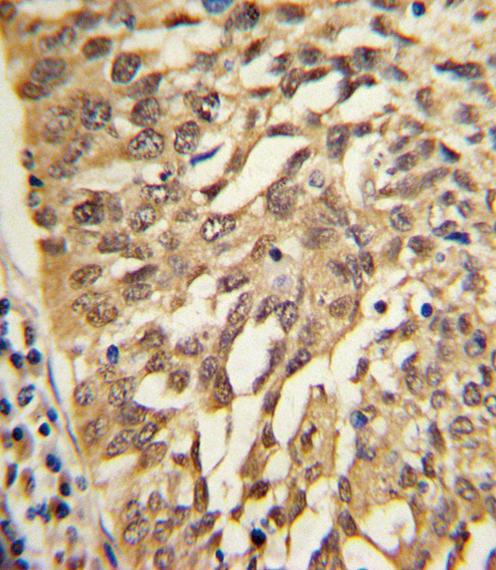

| IHC | 1/100-1/500 | Human,Mouse,Rat |

| Immunogen | This SAR1A antibody is generated from rabbits immunized with a KLH conjugated synthetic peptide between 122-149 amino acids from the Central region of human SAR1A. |